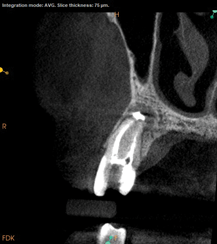

Lastly, regardless of the treatment approach pursued, it is essential to tend to the psychological needs of the patient experiencing a flare-up. The patient should be reassured that the condition is treatable and that flare-ups are quite distinct from treatment failure. In fact, their occurrence has not been shown to affect the overall prognosis of NSRCT (Figure 2 through Figure 5).39,40 Because significant preoperative pain complaints have been associated with a greater risk of flare-up, these patients should be counseled and duly warned of the possible occurrence of a flare-up. Simple discussions on pain management and after-hours emergency availability can significantly reduce the stress of flare-ups for providers and patients alike.14

Fig 2. Case demonstrating successful healing of tooth No. 5 following a flare-up incident. Fig 2: Patient presented with asymptomatic apical periodontitis of tooth No. 5. Fig 3: Following initiation of NSRCT, the patient developed a flare-up with swelling and pain. Amoxicillin was prescribed and the calcium hydroxide medicament was replaced. Fig 4: The patient returned 3 months later with radiographic healing of the apical periodontium. Fig 5: Obturation was completed.

Figure 2

Fig 3. Case demonstrating successful healing of tooth No. 5 following a flare-up incident. Fig 2: Patient presented with asymptomatic apical periodontitis of tooth No. 5. Fig 3: Following initiation of NSRCT, the patient developed a flare-up with swelling and pain. Amoxicillin was prescribed and the calcium hydroxide medicament was replaced. Fig 4: The patient returned 3 months later with radiographic healing of the apical periodontium. Fig 5: Obturation was completed.

Figure 3